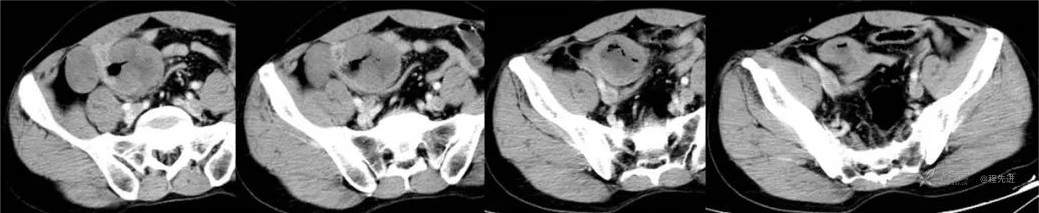

动脉期